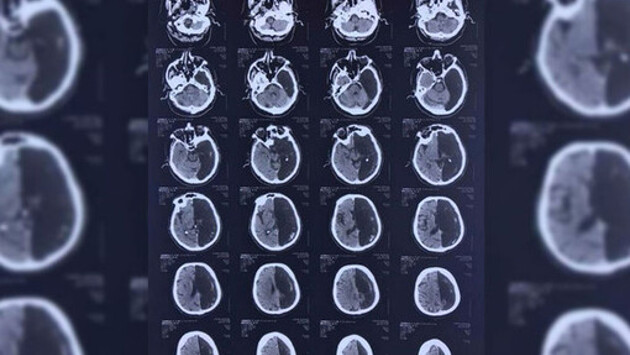

В подмосковную больницу попал пациент с нарушением кровообращения мозга. Когда врачи провели компьютерную томографию, то увидели, что у пациента нет одного полушария. О необычном клиническом случае сообщает «Московский комсомолец» со ссылкой на невролога Федерального центра экстрапирамидных заболеваний и психического здоровья ФМБЦ им. А.И.Бурназяна Марину Аникину.

«Мужчина был доставлен в районную клиническую больницу на юге Московской области в связи с транзисторной ишемической атакой, — рассказала Аникина. — Это преходящее нарушение кровообращения головного мозга по ишемическому типу. В отличие от инсульта при ишемической атаке симптомы не сопровождаются развитием инфаркта мозга (необратимого повреждения участка мозга). У пациента наблюдались проблемы с подвижностью руки и ноги. Когда радиологи сделали ему КТ, то некоторое время пребывали в недоумении — у пенсионера отсутствовала та часть мозга, где произошла та самая ишемическая атака. Вместо левого полушария на снимке зияла черная «дыра». Неврологи сделали вывод, что функции всего мозга у этого человека всю жизнь выполняло только оставшееся правое полушарие».